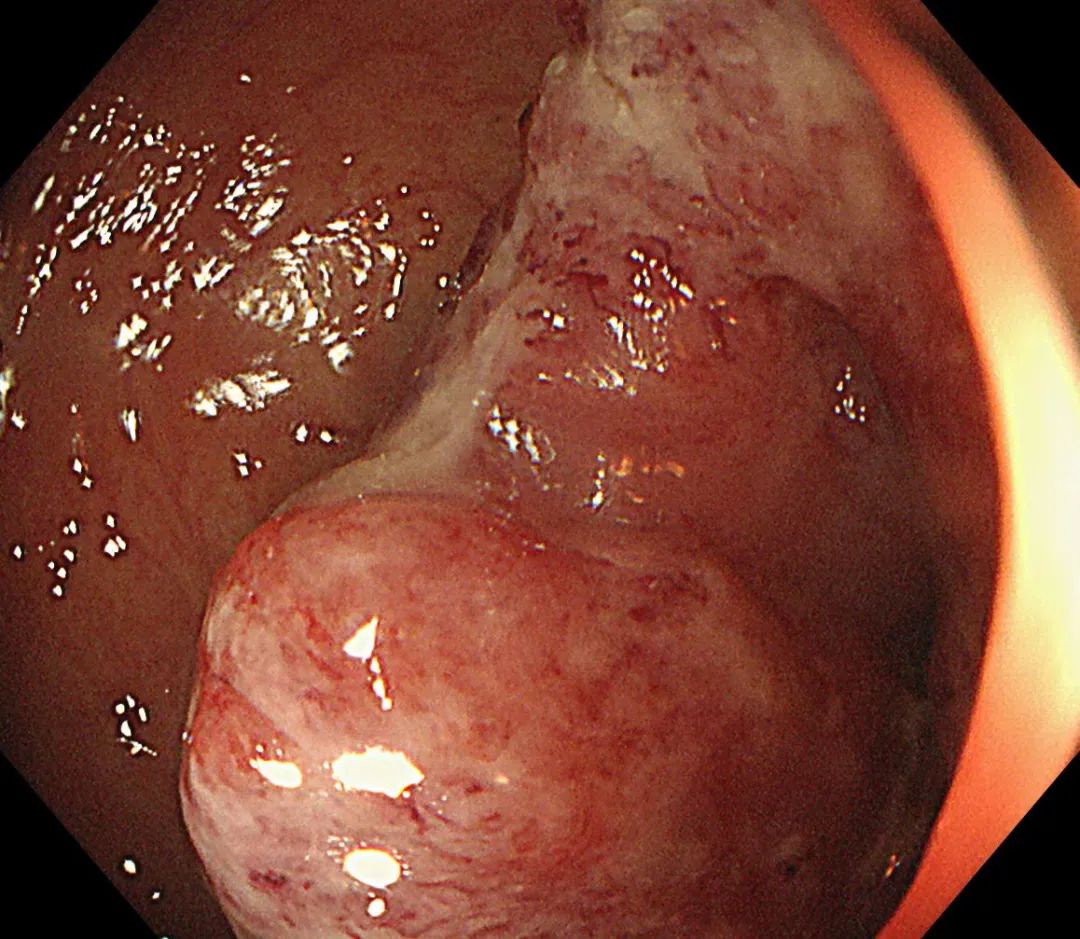

确定诊疗方案后,因患者病情发展较快,消化内科团队为患者开展了急诊肠镜。肠镜检查发现,进镜至距肛缘约 10 cm 处可见一肿物,呈隆起性生长,表面有出血,附有脓苔,考虑直肠恶性肿瘤可能性大,因肠腔水肿、狭窄明显,镜身不能通过,切开刀带导丝进入远端肠道,造影可见肠道呈截断性狭窄。